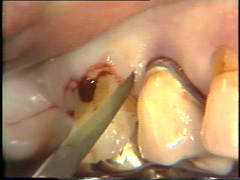

La profundidad al sondaje en los primeros premolares en bucal es poco profunda y aquí la incisión se ubica en el surco ginginval propiamente dicho. El escalpelo se mueve a través del tejido con un serrar suave y con pulso firme. |

En bucal del canino la bolsa es poco profunda y aquí la incisión se ubica más cerca en de la gingiva del diente. En el lateral la insición se ubica más hacia apical de la superficie del diente. |